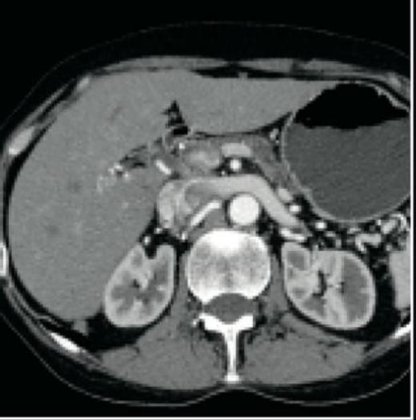

The used GE Discovery CT750 HD CT machine produces high definition images at up to 230 micron resolution, enhancing visualization of smaller structures, for improved diagnostic confidence.

Purchasing a refurbished GE Discovery CT750 HD CT scanner, with GE’s exclusive Gemstone™ detector, will improve your clinical detection and diagnosis imaging capability by up to 33% for body scans and up to 47% in the heart, while decreasing patient radiation dosages by as much as 50%.

LOT 10 OF 35: GE DISCOVERY HD CT SCANNER 64 SLICE DOM: 2011. Description: CT 64 Slice 750 Discovery HD Installed new in 2011 System ID 215762VCT Tube replaced Feb 2017 new Perseus Tube serial 212338GI8, Tube insert 5195900 Housing 60447GM0, Housing model 5195800 Tube mAs 14216232.5 Scan Seconds 599977.099999998 High Voltage Vault replaced same time All Console hard drive have been replaced in 2019 Head Holder Foot board XR-29 Dose Reduction compliant and software loaded NED Multi sync LCD SXI 2 ea GE Console new 2011 Manuals and CD’s included Gantry 127.0.0.1 Patient scans on the tube 23,928 Software version 11MW44.11_SP2-0-13.V40_PS_HD64_G_GTL Brain Perfusion Software 2015 Cardiac Package ILINQ MARS Firmware 01.12.6 Serial # BE273JBAO2 Eaton UPS 9355 Batteries 4-15-2016 GE System main disconnect Cardiac Trigger Monitor IV Biomedical 1108575 Model 3150B QC Phantom MODELGE Healthcare Discovery CT750 HD DescriptionHigh-definition CT system General description High-definition and low-dose CT system, based on GE’s Gemstone CT detector. Special features Features 230-micron spatial resolution, up to 50% lower dose, and improved image quality. Up to 40% improvement in low-contrast detectability. Gemstone Spectral (dual energy) imaging, volume helical shuttle, and coverage up to 312 mm. CT scanner mode Multislice Slices per rotation Up to 128 Other rotation speed options 0.35, 0.37, 0.4, 0.42, 0.45, 0.47, 0.5, 0.6, 0.7, 0.8, 0.9, 1.0 Minimum rotation speed 0.35 sec Gantry diameter 70 cm Minimum temporal resolution 175 msec Maximum beam width 40 cm Minimum room size 20 x 11.5 x 7 Table weight limit 500 Table movement range 170.3 (200.3 option)/43 to 99 cm X-ray generator kV range 80 to 140 kVp Maximum scan range 170 (200 option) cm X-ray tube heat capacity 8.0 MHU POWER CONSUMPTION 150 KVA Clinical applications Up to 50% dose reduction, Gemstone Spectral Imaging, Volume Helical Shuttle Cardiac CTA package Yes Lung nodule package Lung VCAR (option) Brain perfusion package Neuro Perfusion 4 (option), Volume Helical Shuttle Virtual colonoscopy package Advantage CTC Pro (option) FDA clearance status Cleared .